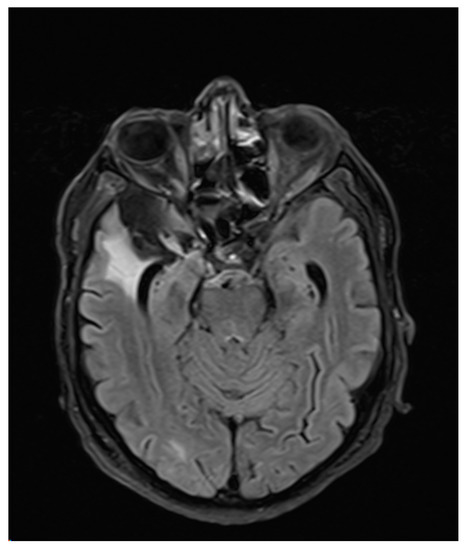

3. Case Report